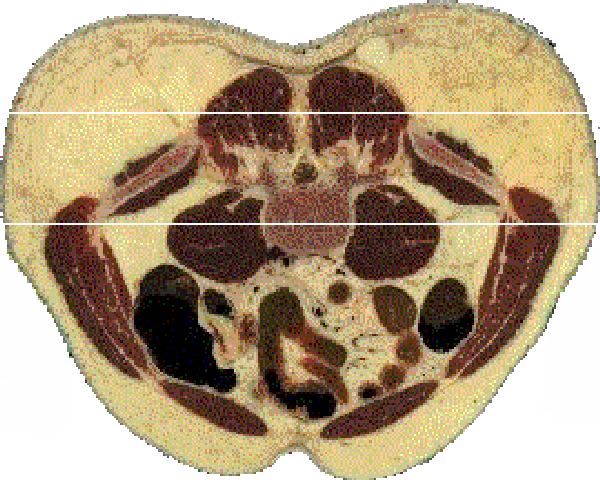

These five transverse sections through the navel clearly display the relationship between the navel and the iliac crests of the hip bones. The sequence of these corporal sections is in transcendent order, representing the order in which the plane of the present engages the navel and hip bones as it steadily moves upward. The bottom section is the initial engagement of the navel and the top section is the final engagement of the navel. Note that as the plane of the present rises through the navel the presence of the hip bone crests diminish to the point of "non-presence" (as indicated between the parallel lines).

These transverse sections of the human are derived from The Visible Human Project utilizing the NPAC Visible Human Viewer. Referred to there as axial views, these sections represent axial views 730, 735, 740, 745, and 750 respectively from top to bottom.

Since the male corpse used in the Visible Human Project is that of an overwieght man, the relationship between the navel and the iliac crests of the hip bones is slightly out of synch. Normally, the "disappearance" of the hip bones aligns with the center of the navel.